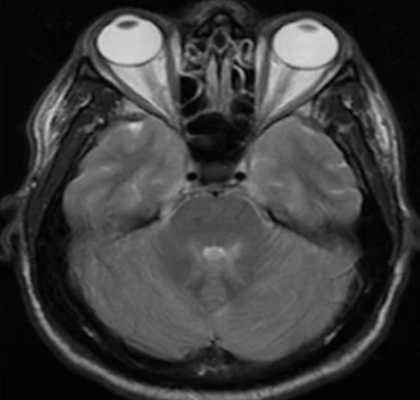

Криптококковый менингит на фоне ВИЧ-инфекции на МР-снимках

Покажет ли МРТ менингит?

Магнитно-резонансную томографию применяют в комплексной диагностике инфекционно-воспалительных заболеваний головного мозга. Процедура позволяет получить послойные снимки органа в трех плоскостях. На изображениях врач может выявить признаки, характерные для воспалительного процесса в оболочках и нервной ткани.

Информация об особенностях патологических изменений помогает определить стадию болезни, подобрать правильную терапевтическую тактику, предотвратить осложнения. Повторные МР-сканирования головного мозга позволяют оценить эффективность лечения, выявить очаги гнойных изменений. Ангиорежим и контрастирование информативны относительно тромбоза сосудов, отека мозга, ранней диагностики инфарктов и инсультов. На вопрос «покажет ли МРТ менингит?» рентгенологи дают утвердительный ответ. Каждый этап развития заболевания имеет характерные МР-признаки. Но диагноз устанавливают на основании результатов люмбальной пункции и анализа ликвора.

При менингите развивается воспаление в мозговых оболочках, сопровождающееся утолщением последних, нарушениями тока ликвора, экссудацией, расширением борозд и межполушарной щели и другими неспецифическими изменениями. Сканирование с контрастом показывает характерное окрашивание очагов воспаления и патологического выпота. МРТ после менингита дает информацию о наличии или отсутствии осложнений, позволяет оценить полноценность восстановления мозговой ткани.